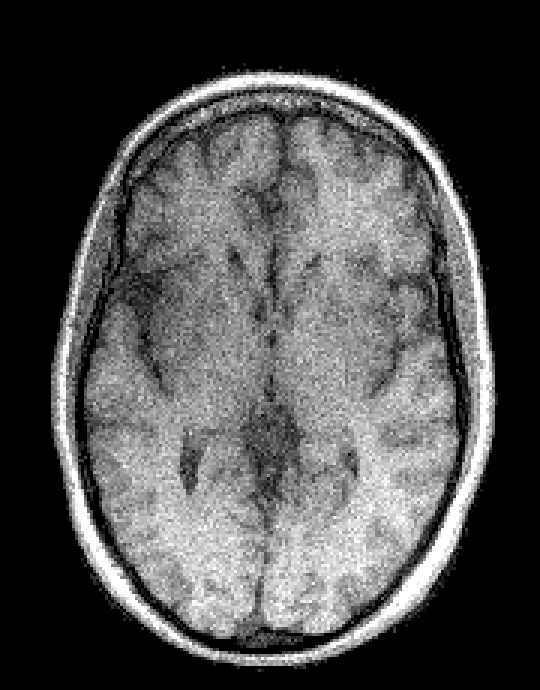

In the second set of evaluations, we considered regularization-based denoising of a 230180 single-channel T1-weighted MR image, obtained by applying complex coil-combination to an 8-channel dataset and subsequently adding simulated complex Gaussian noise. The ground truth and noisy images are shown in Fig. 3.

For reconstruction, the matrix was an identity matrix. Following Refs. [24, 10, 25, 28], the magnitude was regularized using a Huber-function penalty as given by Eq. (28), where a finite difference transformation was used to enforce spatial smoothness of the image. Following Ref. [10, 2, 4, 5, 7], the phase was regularized using a Tikhonov penalty as given by Eq. (29), also using a finite difference transformation to enforce spatial smoothness. All algorithms were initialized with the noisy image.